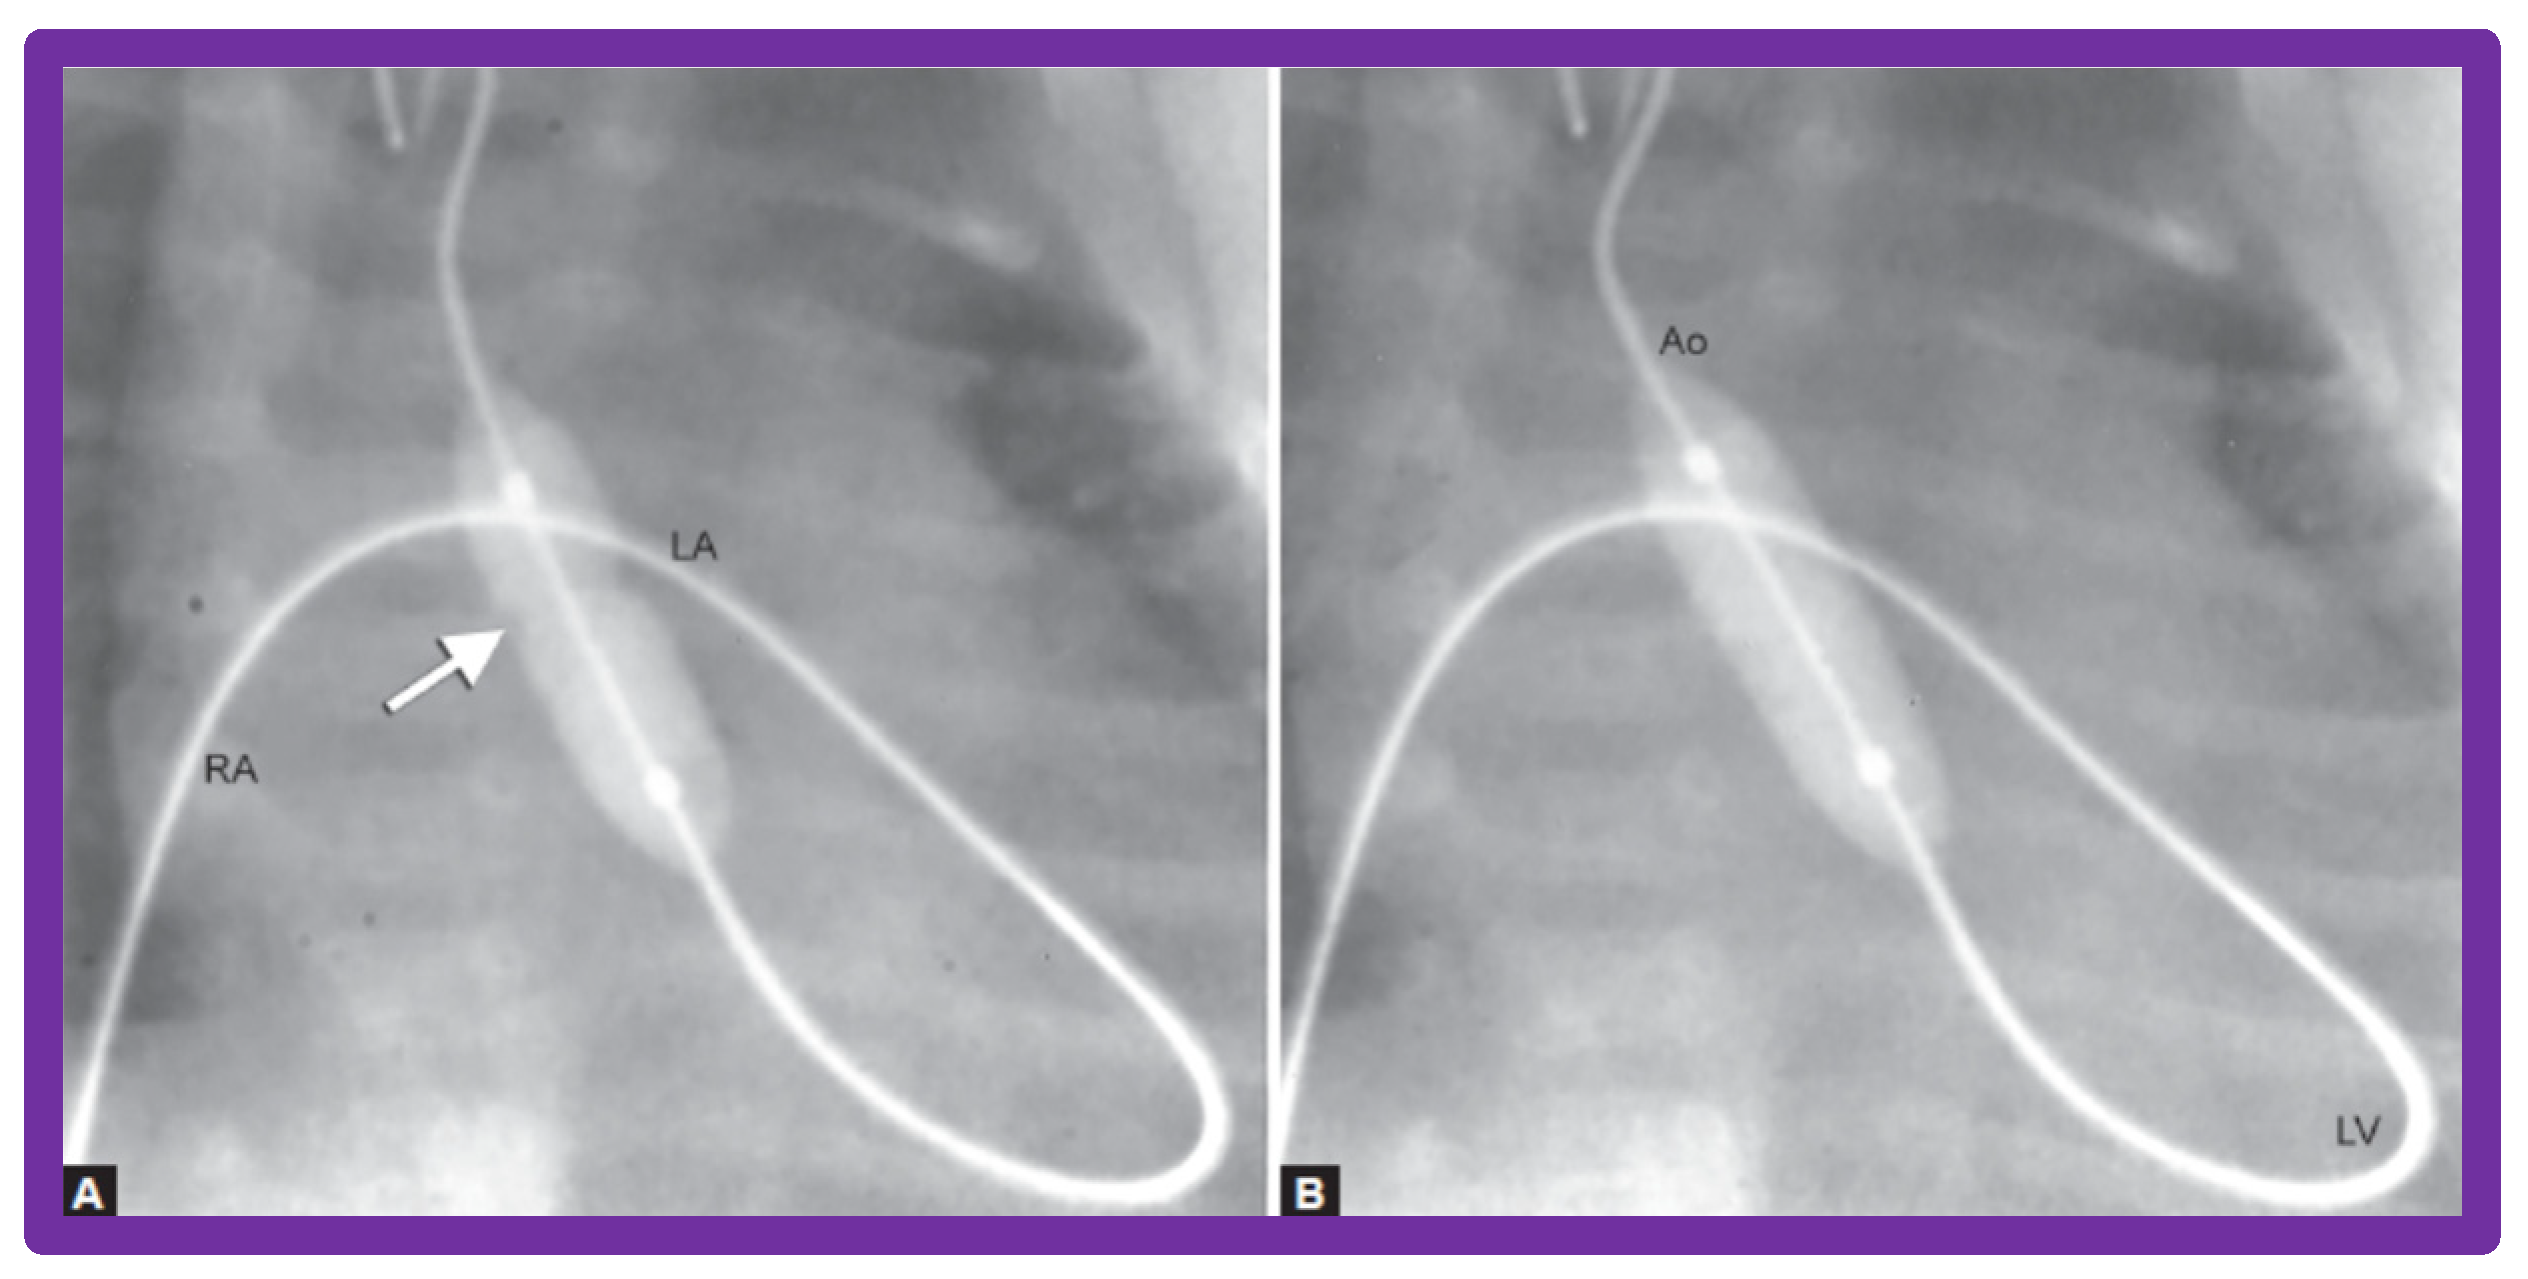

- Rao, P.S.; Jureidini, S.B. Transumbilical venous anterograde, snare-assisted balloon aortic valvuloplasty in a neonate with critical aortic stenosis. Catheter. Cardiovasc. Diagn. 1998, 45, 144–148. [Google Scholar] [CrossRef]

- Rao, P.S. Anterograde balloon aortic valvuloplasty in the neonate via the umbilical vein. Card. Cardiovasc. Interv. 2003, 59, 291–292. [Google Scholar] [CrossRef] [PubMed]

- Rao, P.S. Role of interventional cardiology in neonates: Part II-Balloon angioplasty/valvuloplasty. Neonatol. Today 2007, 2, 1–12. [Google Scholar]